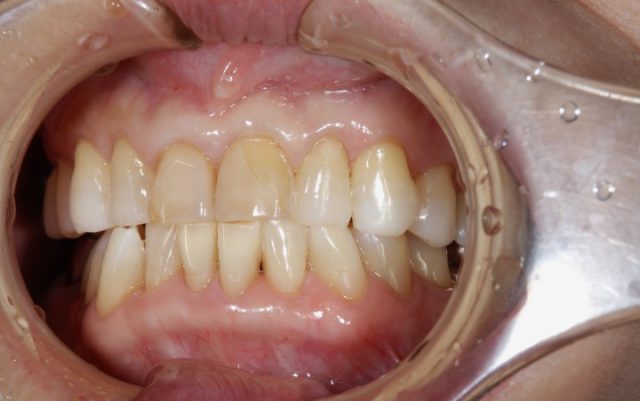

施術後

術後の画像を見ていただいても分かりますようにまわりの歯と比べてもとても自然に仕上がります。おそらく近くでじっと見られても被せものであるとは分からないほど自然です。患者さまご本人も被せ物の仕上がりにとても喜んでおられました。